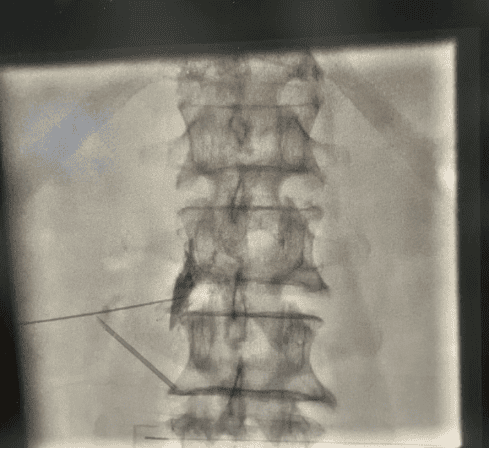

为进一步明确病因,医疗团队为患者施行了诊断性神经阻滞治疗。治疗后,其疼痛症状奇迹般暂时消失,这一阳性反应精准锁定“责任神经”为L2/3阶段,不仅为后续治疗指明了方向,也极大增强了患者对团队的信任。

(诊断性神经阻滞明确责任节段)